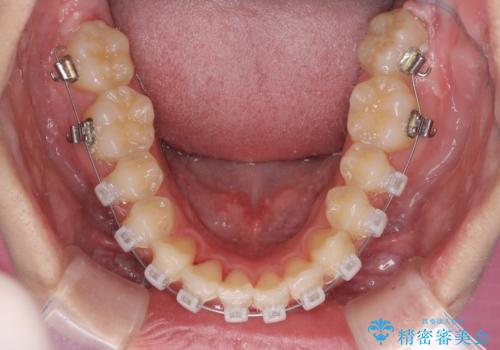

- 矯正装置

- クリアブラケット

ぱっと見はインビザラインによる矯正治療も可能と思われましたが、歯根が最も長い犬歯がクロスバイトになっており、インビザラインでは対応困難と判断され、ワイヤー装置にて矯正治療を行うこととしました。

クロスバイトになっている犬歯は、歯の移動に伴い装置を張り替えていくことで対応することとしました。